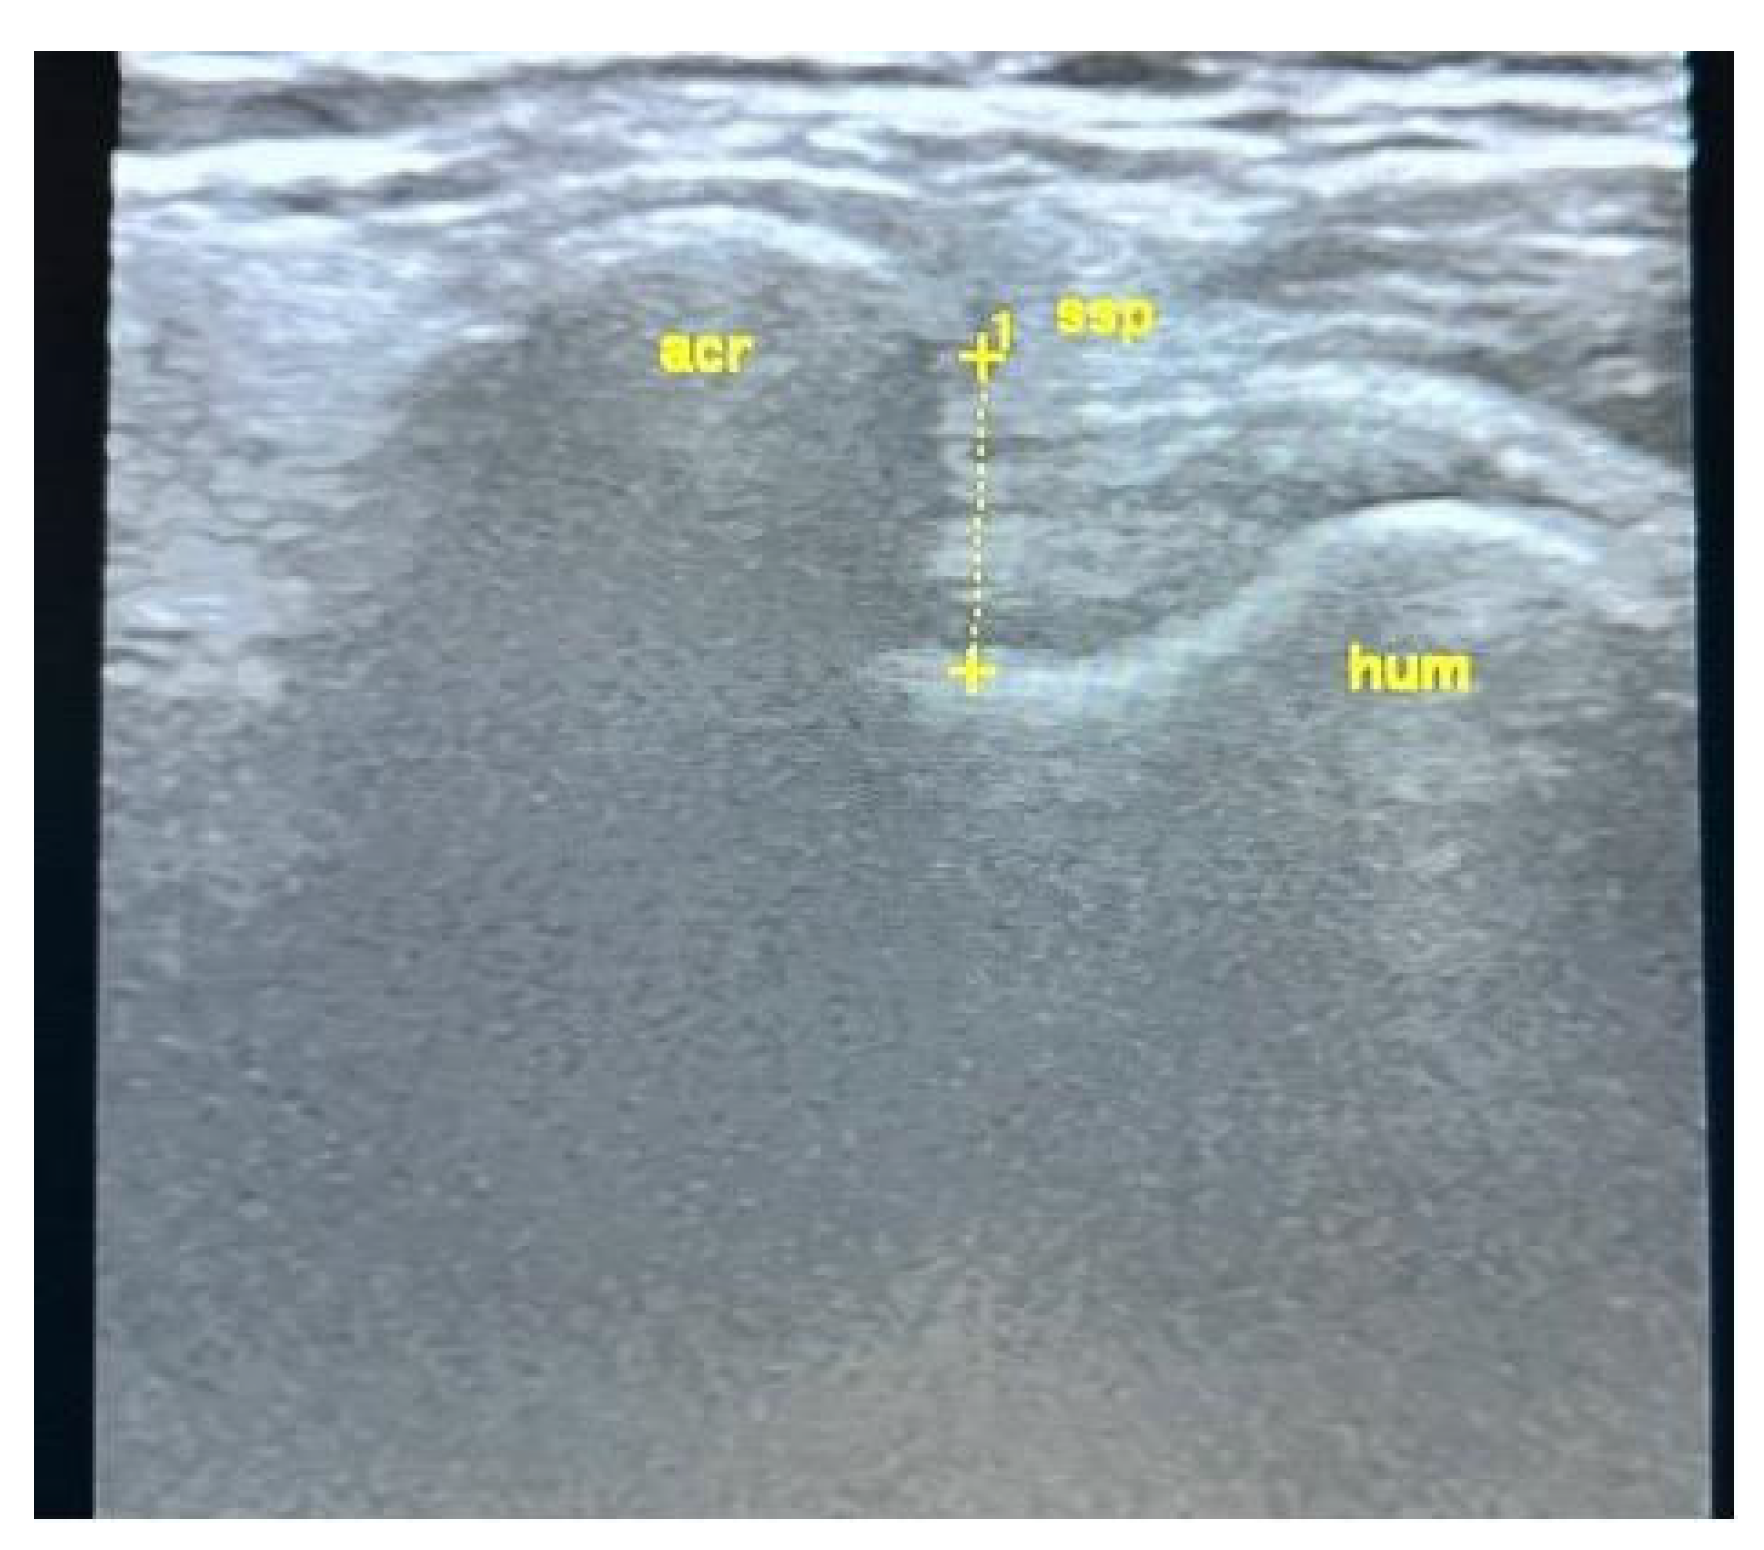

All USG evaluations were performed by a physical medicine and rehabilitation specialist with +30 years of experience in musculoskeletal USG using a GE LogiqP6 Pro device GE Ultrasound Korea, Gyeonggi, Republic of Korea and a linear transducer. Imaging was performed using standard shoulder sections while the patients were in a sitting position with an elbow flexed and an arm internally rotated and laid on the anterior thigh. We laid the probe on the coronal plane on the acromio-clavicular joint. We then moved it laterally to detect acromial-end and subacromial structures, including the subacromial bursa (SB), rotator cuff, and humeral head. Beneath the SB is the supraspinatus tendon (SSp), which attaches to the tuberculum majus of the humerus. The arm was rotated and abducted to examine the tendinous integrity and motion of the SSp. To measure the AHD and ensure standardization, a perpendicular line was drawn from the most lateral tip of the acromion to the head of the humerus, yielding an automatic value via USG-software vR2.0.5 (Figure 2 and Figure 3). In this position, we evaluated the supraspinatus and RC and measured their thicknesses on the short axis. The thickness of the SB was noted. Then, the probe was retracted, and the internal structure of the infraspinatus (Isp) and its thickness were measured. Notably, the teres minor, though difficult to discriminate, is at the posterior end of the ISp. Then, the probe was moved to the short axis to examine the biceps tendon. Here, the probe was turned to the longitudinal axis to evaluate the long biceps tendon and determine its thickness. The probe was then moved to the back side on the short axis to examine the labrum, glenoid bone, humeral head, and joint capsule. If the probe is turned longitudinally, the muscle bellies and myo-tendinous junctions of the RC muscles can be seen. Subsequently, the arm was externally rotated, and the probe was again placed medial to the biceps tendon to expose the tuberculum minus, subscapularis tendon, and anterior acromion, along with the coracoacromial ligament. Then, we positioned the arm posteriorly on the back pocket. The measurements regarding the SSp, Isp, and RC were repeated and recorded. During the examination, the acromioclavicular joint, RC tendons (supraspinatus, infraspinatus, subscapularis, and teres minor), long-head biceps tendon, SB, and related structures were evaluated in all planes. Tendon thickness, the presence of subacromial effusion, ruptures, tendinous degeneration, contour irregularities, RC integrity, and homogeneity were examined. Measurements were performed before (baseline) and after the treatment (post-tr).

Figure 2. USG AHD measurements. See text.